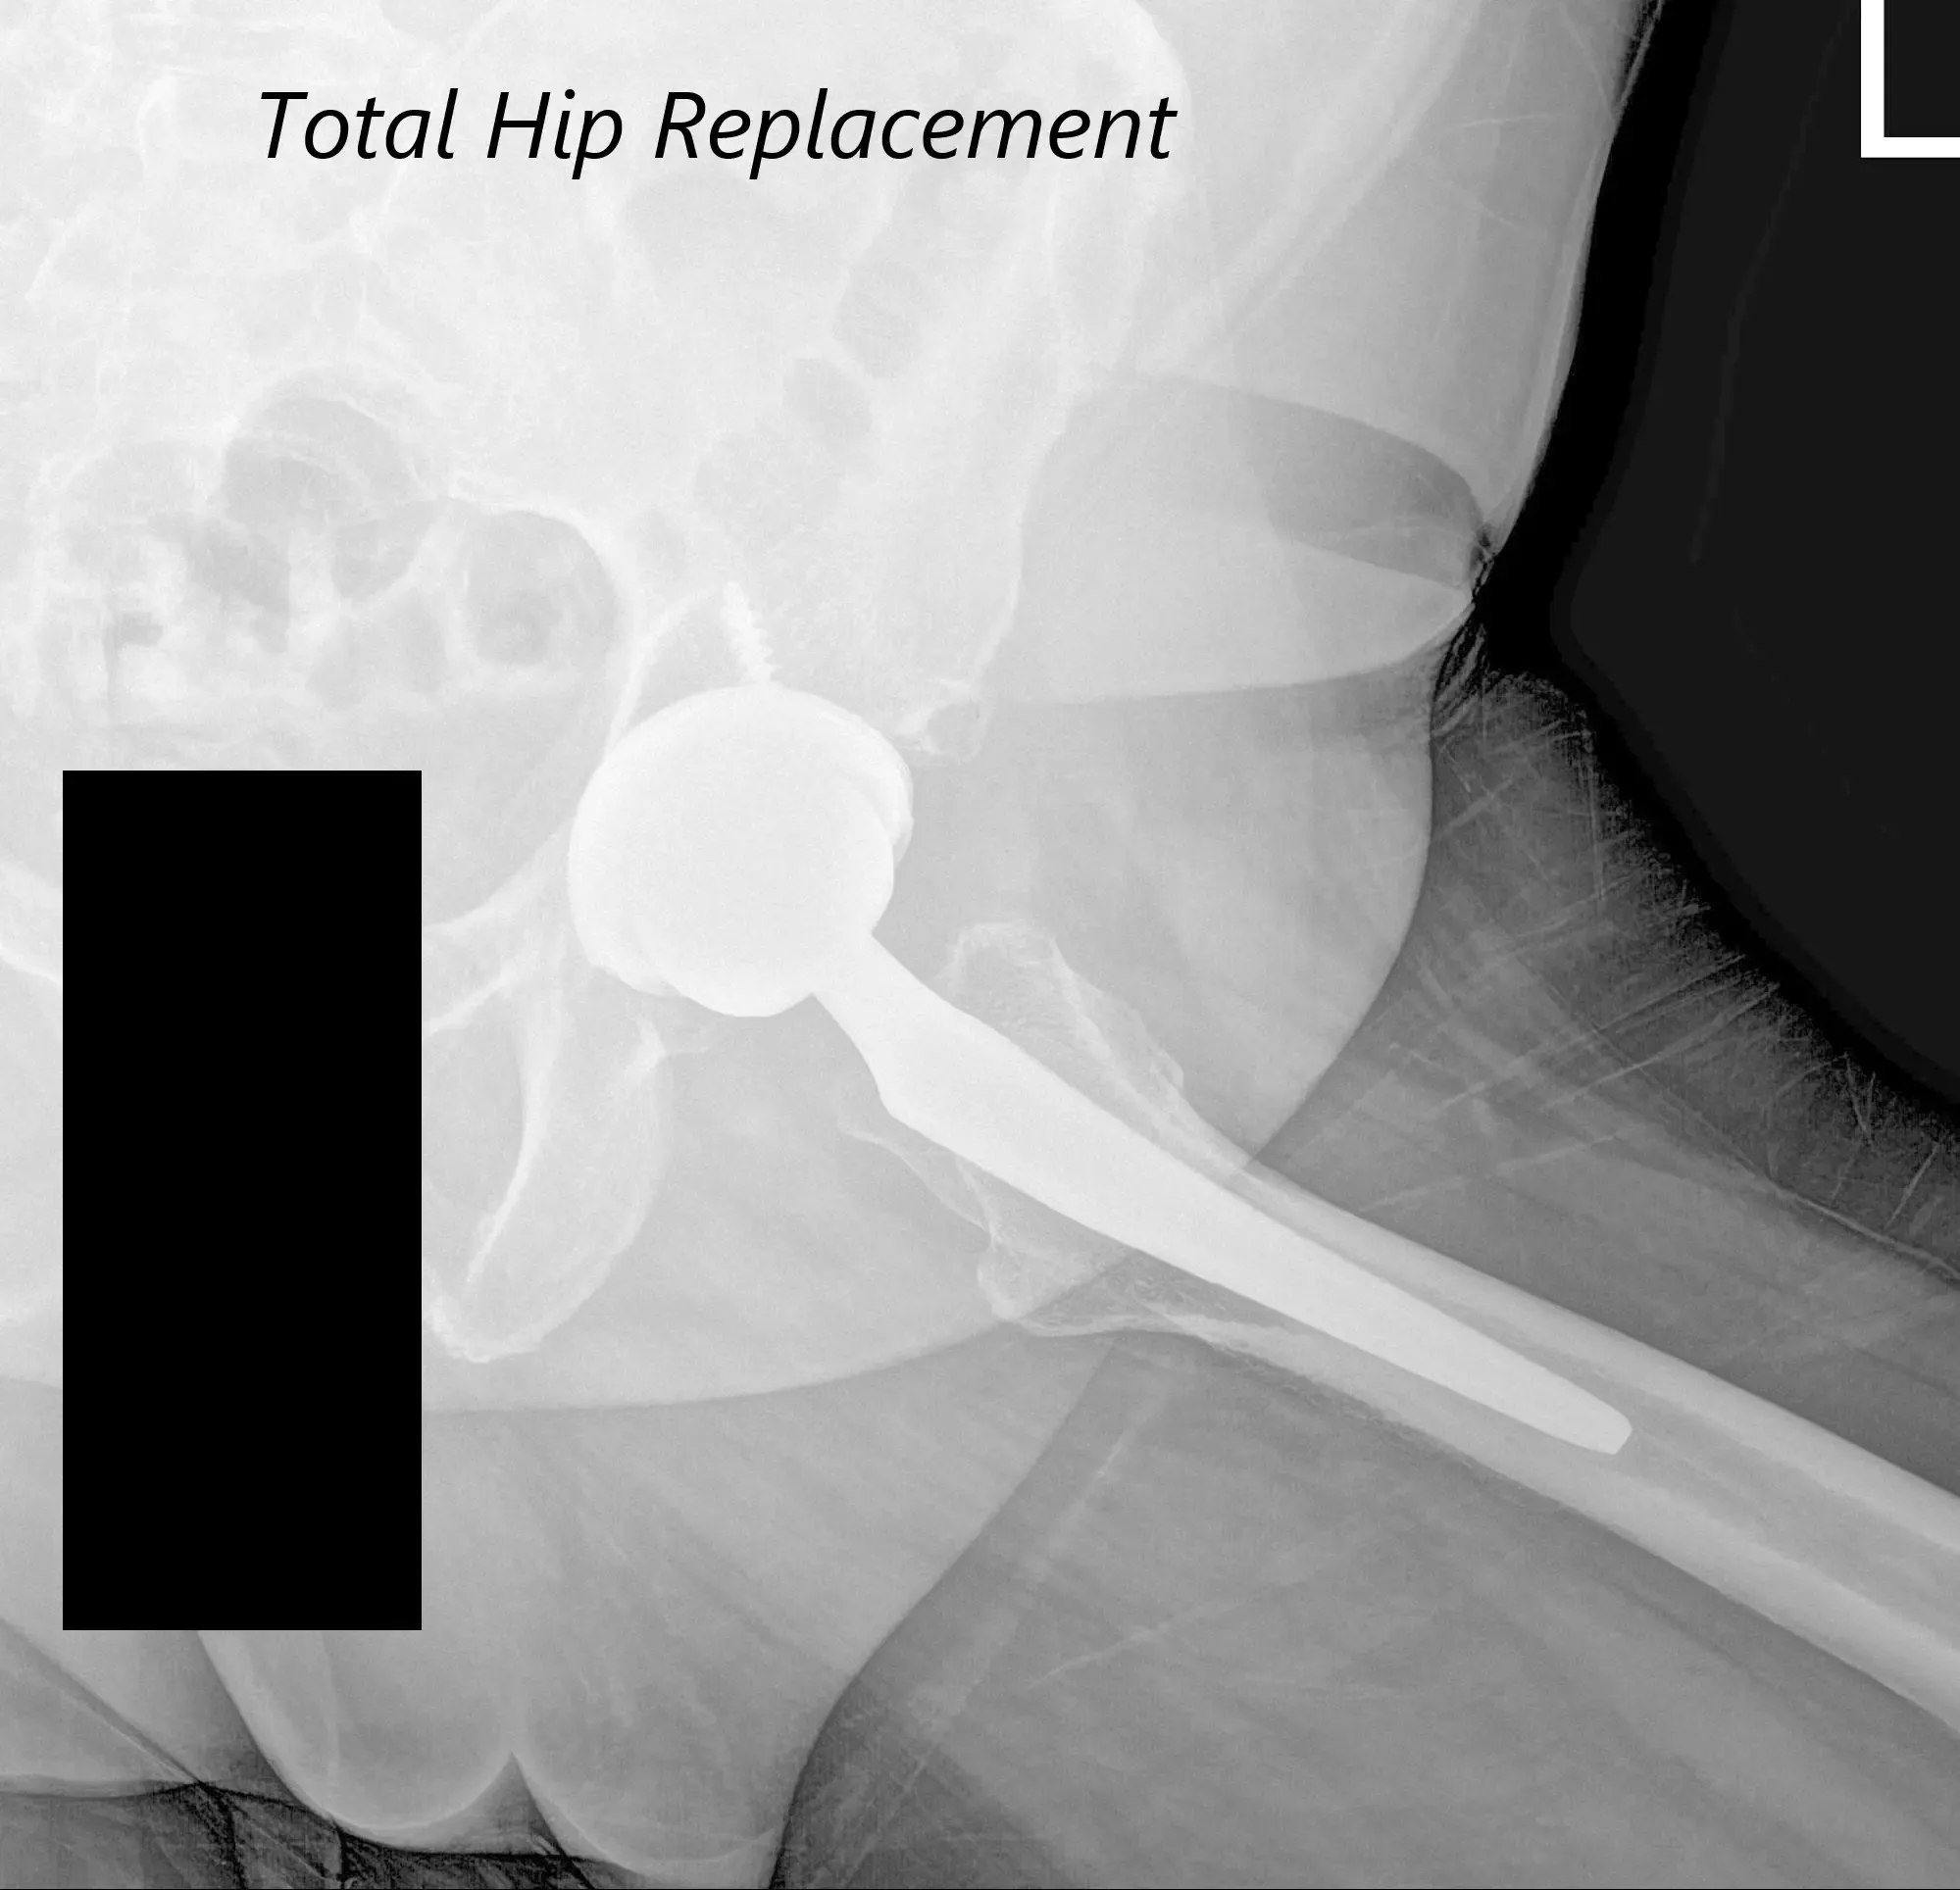

Postoperative AP view of the Pelvis X-ray showing both hip joints with frog-leg lateral views of the right and left hip joints.

After the procedure, x-rays were obtained and were then saved to the PACS system. The alignment and stability on the x-ray was found to be acceptable. The patient was transferred to the postoperative care unit in stable condition.